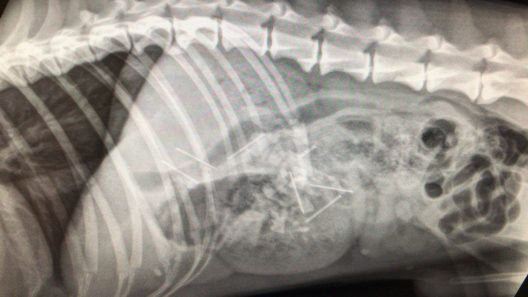

Am Wochenende wurden in die  Tierklinik Sonnenhof in Derendingen SO gleich drei Hunde eingeliefert, die präparierte Cervelats gefressen hatten. Trotz sofortiger und erfolgreicher Not-Operation verstarben die Hunde. Alle drei Hunde gehörten einer Frau aus dem bernischen Rohrbach.

Nun hat die Kantonspolizei Bern am Montag in einem Garten in Rohrbach verdächtige Substanzen sichergestellt. Es dürfte sich nach ersten Erkenntnissen um die Reste von Fleischstücken handeln, die mit giftigen Stoffen und gefährlichen Gegenständen versetzt worden waren.